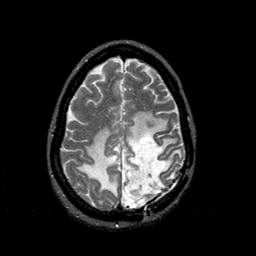

MR Study #1 -- Slice #39